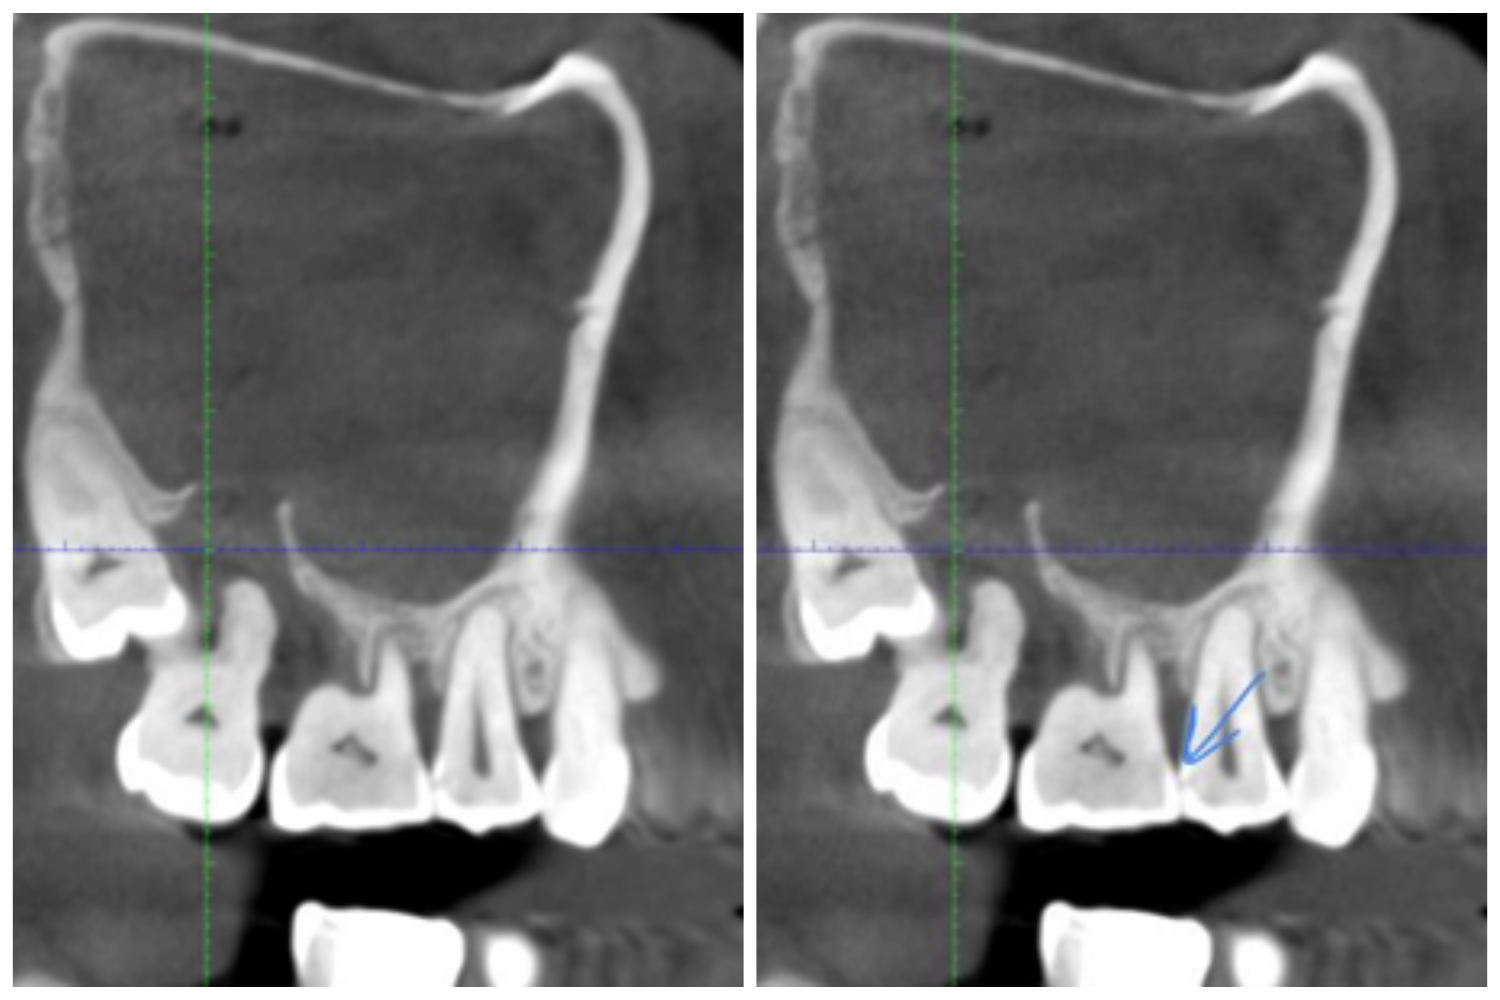

И у него же есть ещё одна очень интересная, но куда более частая картинка:

Тут интересен не только зуб, открывший ворота в пазуху

Посмотрите на маленькую точку по стрелке. Это может быть как дефект снимка, так и кариес.

Как отличить? Через знание анатомии. Мы знаем, что это самое вероятное место для кариеса в контактном пункте, поэтому ставим на то, что это он и есть. Статистически вероятность появления в этом месте единичного дефекта куда меньше, чем вероятность кариеса. Открываем пациента — конечно же, это кариес и есть. Кариес здесь — случайная находка, а причина — карман у седьмого зуба, это тот, что через один слева, видно отсутствие кости вокруг.